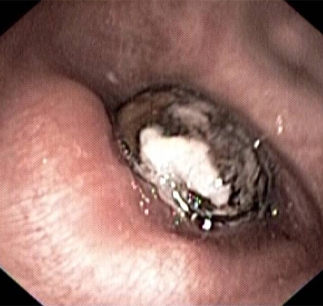

Bronchoscopy image showing a loquat seed completely occluding the bronchus intermedius

From the personal collection of Dr S. Murgu and Dr H. Colt, University of California at Irvine Medical Center